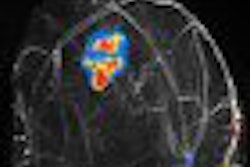

MROpen's U-shaped design is intended to optimize image quality in all anatomic regions through its transverse horizontal field. It also features a wide gantry and an open top to minimize claustrophobia and allow more flexibility in patient positioning.